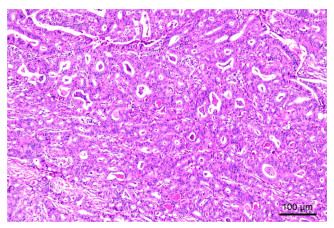

•   Objective  Pulmonary adenocarcinoma high-grade components include micropapillary type and solid type, and high-grade components ≥20% are defined as poorly differentiated and are independent predictors of poor prognosis. Lobectomy is recommended. In this study, four kinds of deep learning models were used to predict poorly differentiated adenocarcinoma, and the diagnostic efficiency of each model was compared to find the best model to improve the prediction accuracy of poorly differentiated adenocarcinoma.  Methods  Retrospective analysis of 253 lung adenocarcinoma lesions confirmed by pathology at the Affiliated Traditional Chinese Medicine Hospital of Southwest Medical University from October 2021 to March 2024. The CT images were preprocessed and abnormal data screened, then the training, validation, and EfficientNet test sets were divided in the ratio of 8∶1∶1 and fed to the four models of ResNet, MobileNet, DenseNet, and EfficientNet for high-level component prediction.  Results  The AUC values of the four models, ResNet, MobileNet, DenseNet, and EfficientNet, are 0.757, 0.872, 0.877, and 0.812, respectively. DenseNet showed excellent performance in this task. Accuracy, Precision, Recall, and F1-Score were 84.97%, 84.26%, 83.28%, and 84.67%.  Conclusion  Four kinds of deep learning models have a good predictive effect on high-grade components of lung adenocarcinoma, and the DenseNet model has higher predictive accuracy.